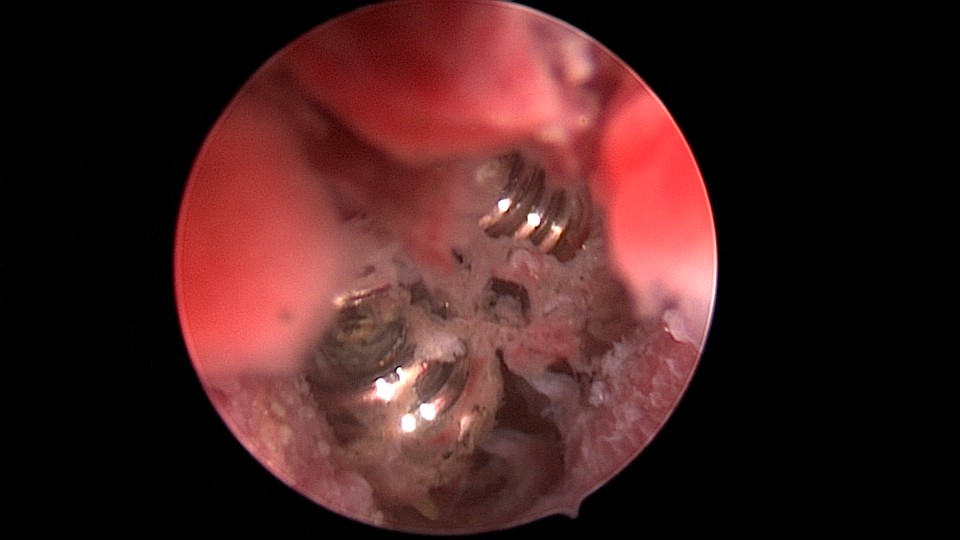

患者49岁,G1P1,顺产1次。安环13年,月经紊乱1月,外院取环失败。B超提示O型环嵌顿,宫腔镜见宫颈管及宫腔组织充血,宫腔广泛粘连,节育环嵌顿、扭曲,异物钳配合中弯钳拉出节育环,环变形、断裂,宫壁节育环嵌顿处见割裂痕迹,无出血,检查宫腔各部,无节育环残留。

图片发自160App